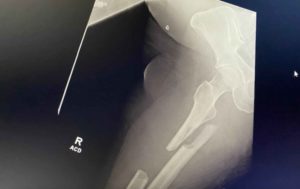

When she called me, of all her injuries, it was the broken left arm that was the most painful. Fracturing the wrist and elbow, she explained that she had Complex Regional Pain Syndrome, and described it like a sunburn, with acid being put on it. Fortunately, she had already recovered from 13 years of chronic pain with Block Therapy and knew how to breathe. She shared that this was her saving grace during the month in the hospital.

The prognosis wasn’t good. They suspected she wouldn’t walk again and never be able to have normal function with her left hand. Here are some photos showing the extent of her fractures at the time of injury.